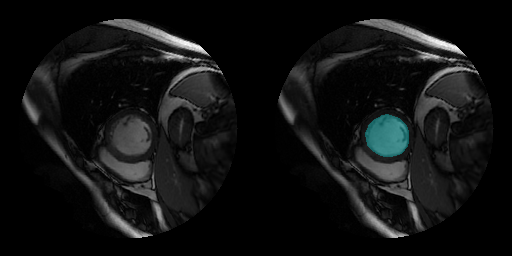

Sunnybrook Cardiac Data set

| The Sunnybrook Cardiac Data set contains cine MRI images and ground truth labels of the left ventricle [28]. The data set contains images from multiple patients with various cardiac pathologies. The MRI images are in the DICOM file format and the label images are in the PNG file format. This code downloads a subset of the original data set from the MathWorks website. The subset contains MRI images and label images from 45 patients. The total download size is approximately 105 MB. zipFile = matlab.internal.examples.downloadSupportFile("medical","CardiacMRI.zip"); filepath = fileparts(zipFile); unzip(zipFile,filepath) The

imageDir = fullfile(filepath,"Cardiac MRI");

For an example showing how to process this data for deep learning, see Cardiac Left Ventricle Segmentation from Cine-MRI Images Using U-Net Network. | Semantic segmentation |